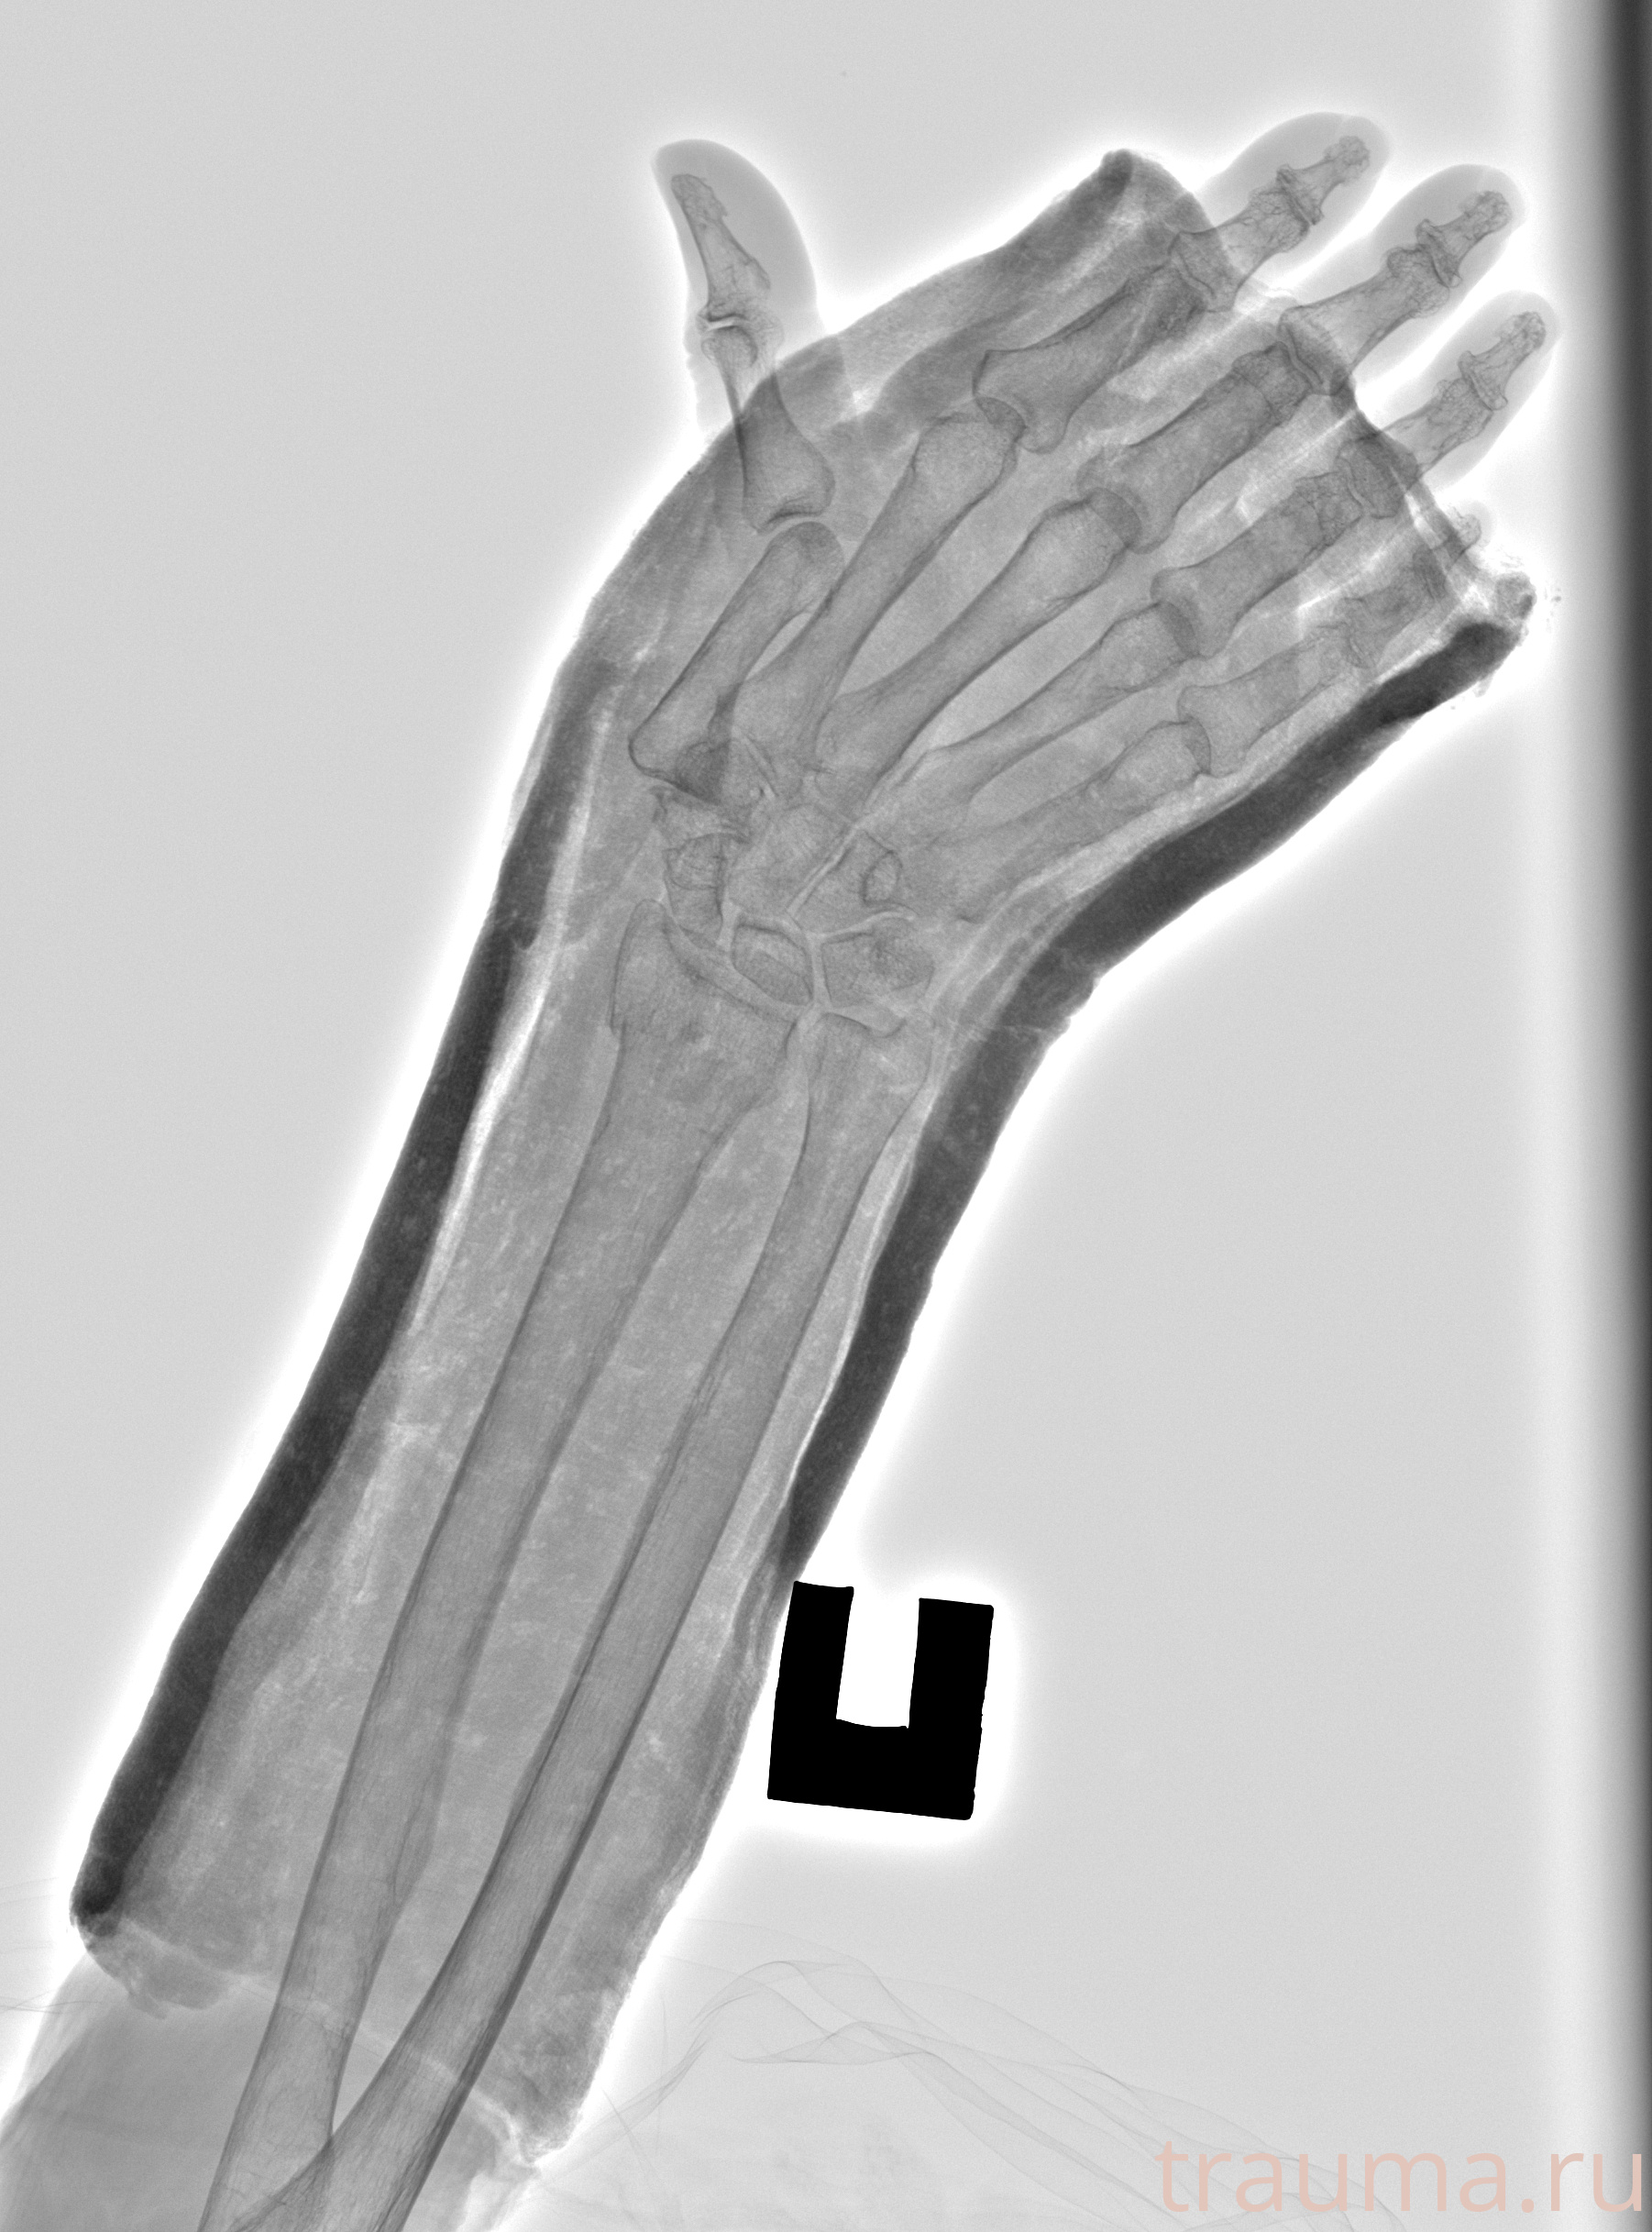

Рентген на дому: по вашему адресу приезжает врач-рентгенолог, травматолог-ортопед с мобильным рентгеновским аппаратом, проводит диагностику травмы или заболевания, делает необходимые рентгенограммы, дает рекомендации по дальнейшему лечению. Получить качественные снимки в домашних условиях возможно благодаря уникальной методике, разработанной МосРентген Центром для института  Склифосовского